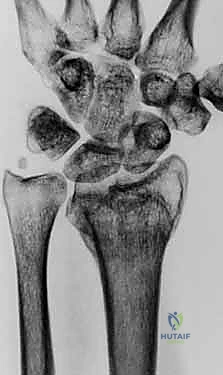

- الأشعة السينية الرقمية (X-rays): للرسغين السليم والمصاب، لمقارنة الزوايا وحساب مقدار التشوه بدقة.

- الأشعة المقطعية (CT Scan) مع إعادة البناء ثلاثي الأبعاد (3D Reconstruction): هذه الخطوة حاسمة. تتيح للدكتور هطيف رؤية العظم من جميع الزوايا، وتحديد مكان القص بدقة متناهية.